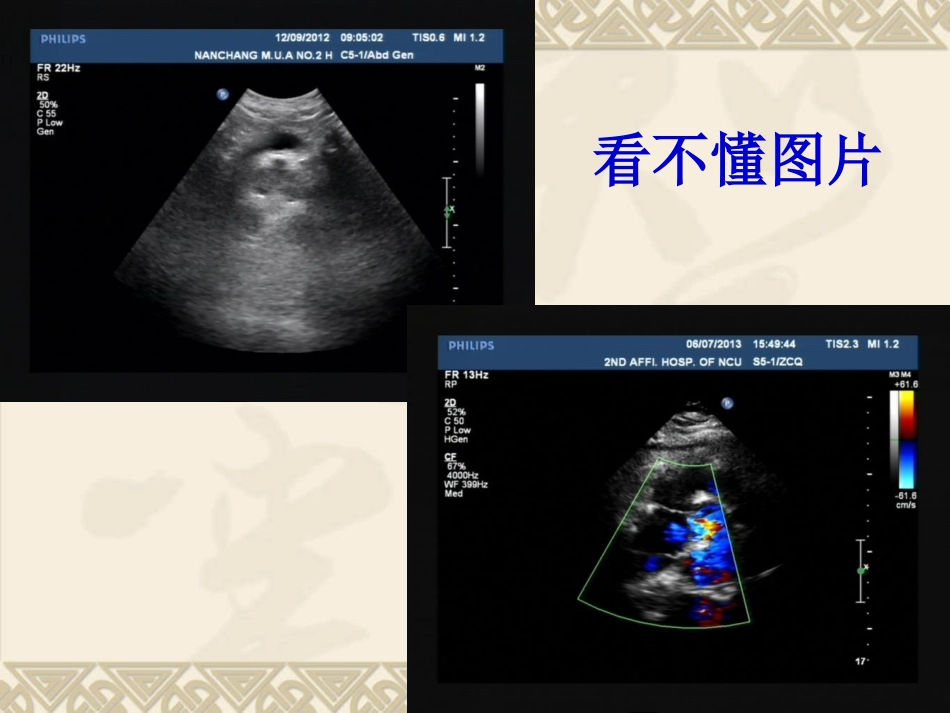

临床反映问题超声图片不清晰报告自相矛盾图片无标示图像无标示看不懂图片超声描述与图像不符合存在问题(2012年12月-2013年4月)月份总数(例)图像未标记(例)废图(例)描述不规范(例)未填数据(例)不合格率123601118.3%013621008.3%0245701017.8%0338211010.5%0438400010.5%计划(Plan)按三甲要求对超声报告及图像进行质量管理及原因分析,提出整改措施。控制目标:提高超声报告的质量,确保超声报告准确、规范和标准,最大限度的减少报告的不合格率(<5%)。每月随机抽取40-50份超声报告,对其进行评价和分析。病人因素透声条件差病人数量多新仪器标示意识弱审核不仔细标示键失灵不熟悉工作站配合不默契仪器因素学生因素医生因素超声不合格报告原因分析超声不合格报告原因分析仪器不熟悉基础知识差不合格超声报告原因分析0481216202428320.00%20.00%40.00%60.00%80.00%100.00%不良例数累计影响度超声科19位医生不合格报告所占比例医生129%医生213%医生310%其他医生48%实施(Do)强调规范化、标准化超声报告重要性每个月对超声报告进行随机抽查、总结分析及科室点评针对性学习:如何规范采图单独与不合格率较高的医生谈话实施(Do)超声图像PDCA进度表2013年3-13-314-305-306-297-298-289-2710-27查找超声报问题分析问题原因改进阶段检查阶段巩固阶段开始日期完成时间月份总数(例)图像未标记(例)废图(例)描述自相矛盾(例)描述不规范(例)未填数据(例)不合格率2457010017.8%3382101010.5%4384000010.5%538011017.9%638201007.9%736200005.6%854001013.7%954001103.7%检查(Check)(2013年2月-9月)检查(Check)0.00%2.00%4.00%6.00%8.00%10.00%12.00%14.00%16.00%18.00%2013年2月2013年4月2013年6月2013年8月2013年10月超声报告不合格率系列1总数图像未标记废图描述自相矛盾(例)描述不规范未填数据不合格率(例)(例)(例)(例)(例)改进前19515321111.28%改进后242504114.55%051015(例)(例)(例)(例)(例)图像未标记废图描述自相矛盾描述不规范未填数据改进前后不合格原因对比改进前改进后检查(Check)超声科19位医生不合格报告所占比四腔心对比图颈总动脉斑块对比图ASD对比图持续改进措施(Action)坚持标准化图像采集及图像标示;要求每位医生认真检查每份报告,降低不合格率,提高报告的准确性。坚持每个月对每位医生的超声报告质量进行抽查,并在科室周会上进行通报,并把它列为科室考核指标之一。持续改进措施(Action)051015(例)(例)(例)(例)(例)图像未标记废图描述自相矛盾描述不规范未填数据改进前后不合格原因对比改进前改进后★针对描述自相矛盾、图像未标记等主要问题进一步持续改进,进入下一个PDCA循环不合格率11.28%改进不合格率<2%不合格率<5%不断改进APDCAPCDACPD改进